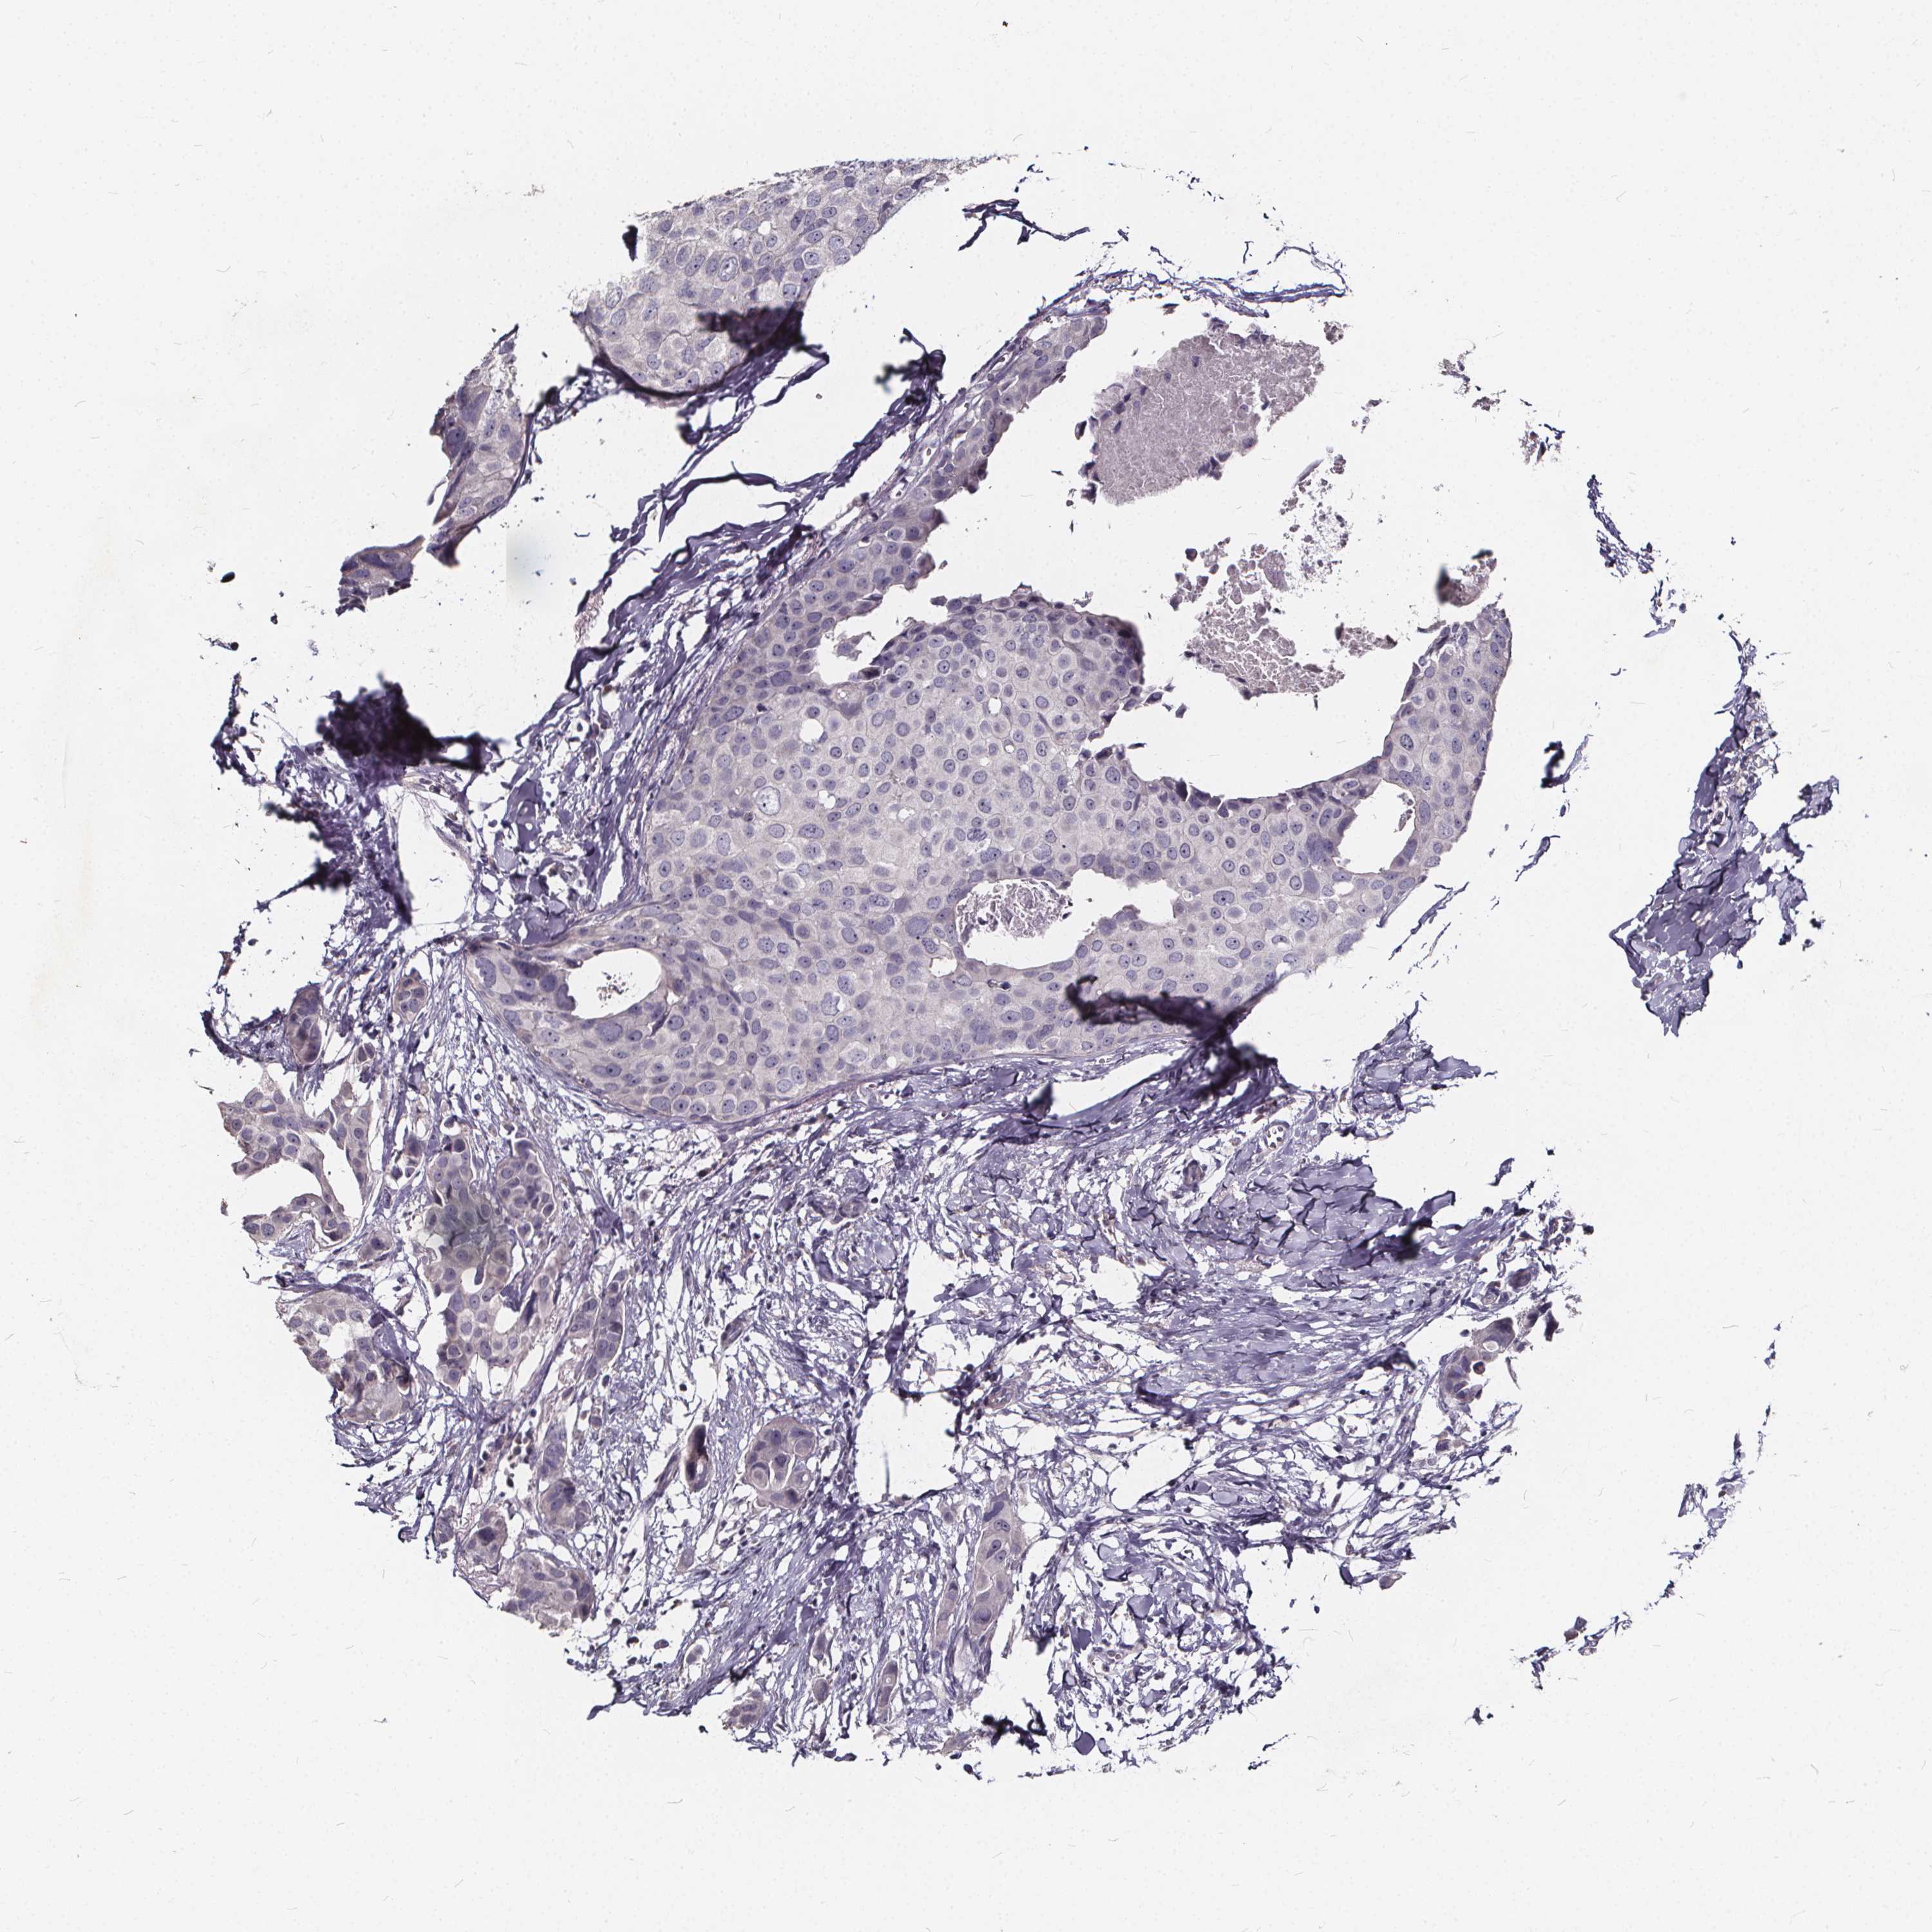

CANCER BREAST CANCER Show tissue menu

BRCA TCGA BRCA VALIDATION PROTEIN EXPRESSION